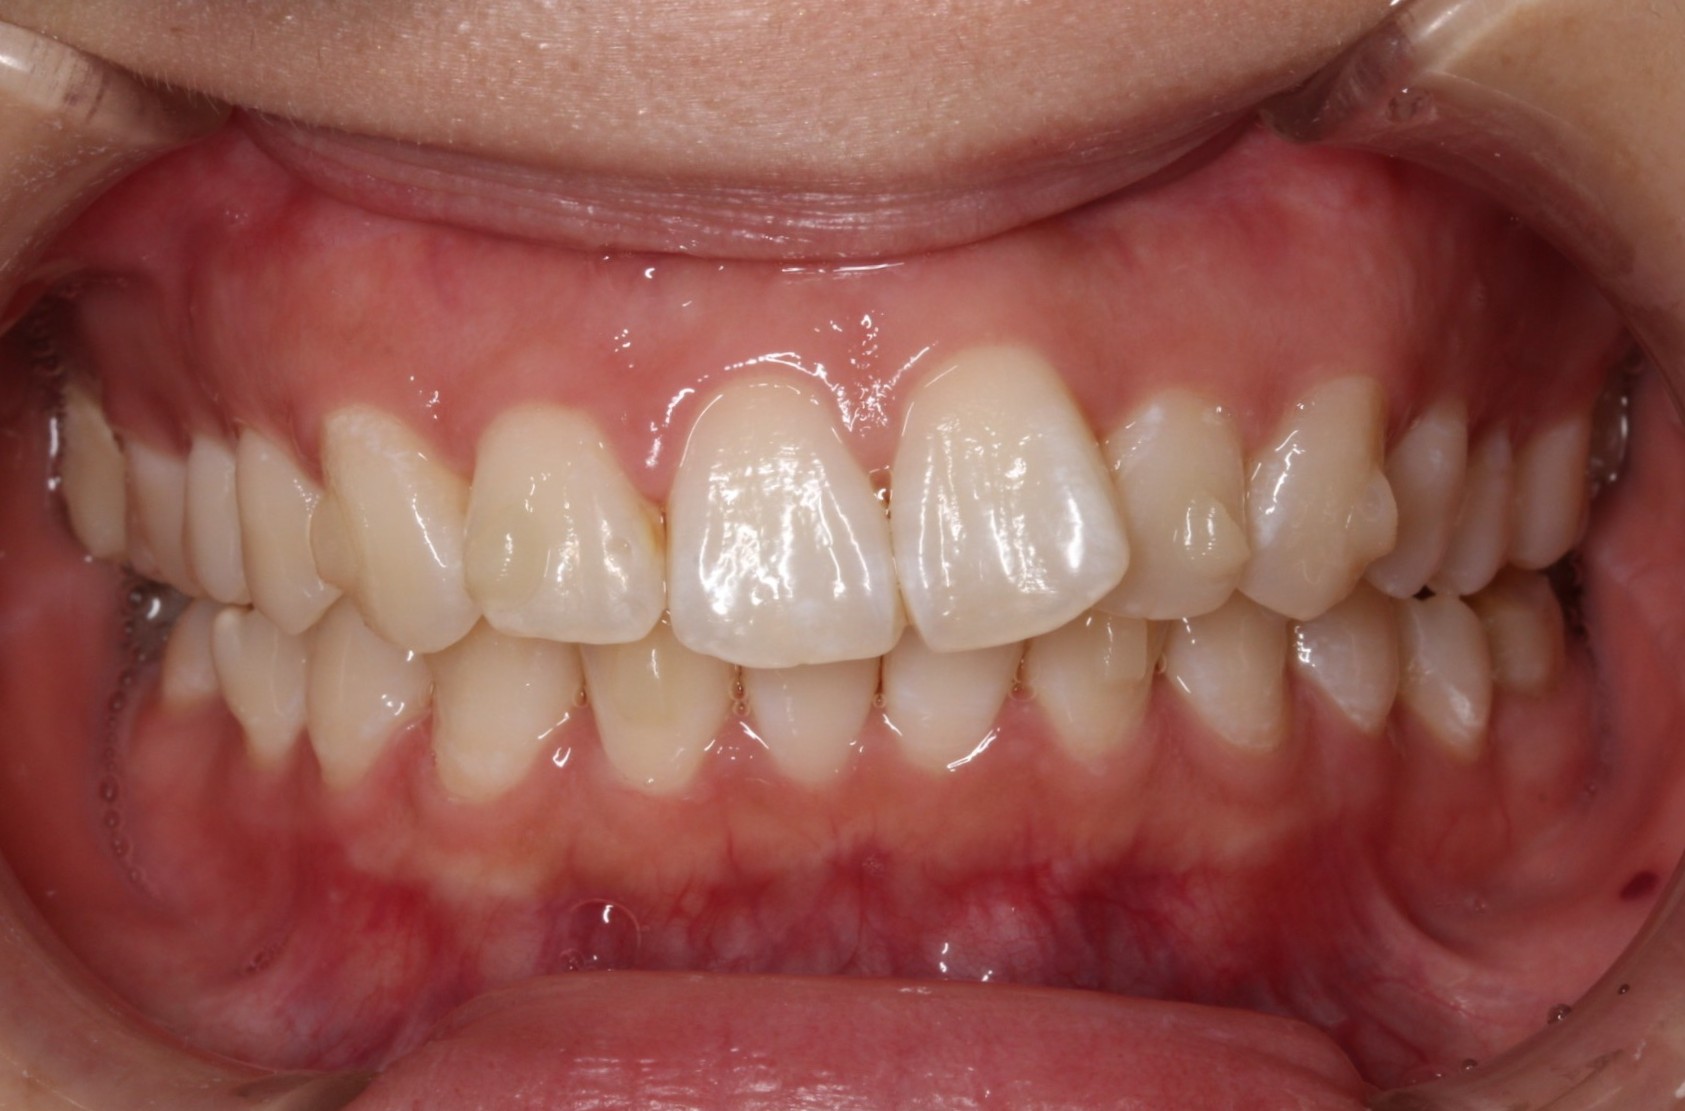

矯正術前:正面

矯正術後:正面